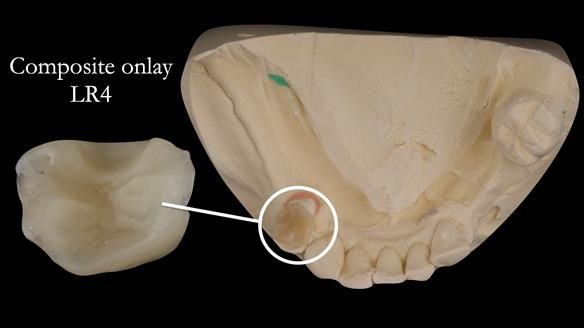

- Composite onlay lower right first premolar – designed to support new lower RPD